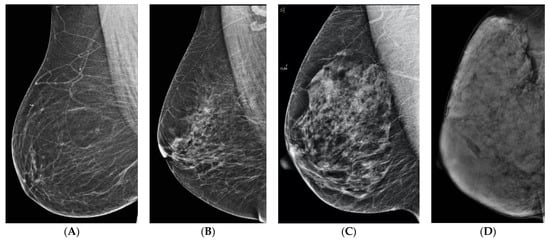

6. Digital Breast Tomosynthesis (DBT)

7. Magnetic Resonance Imaging (MRI)

8. Contrast-Enhanced Mammography (CEM)

9. Molecular Breast Imaging (MBI)